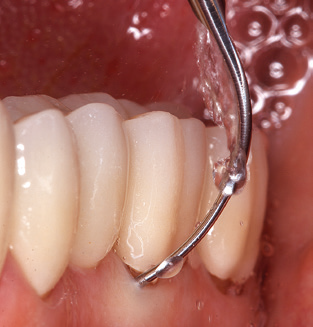

Dopo la pulizia meccanica delle superfici dei denti e degli impianti, le superfici dei denti naturali vengono pulite manualmente utilizzando strumenti manuali standard. Quando si esegue la pulizia manuale, è necessario prestare particolare attenzione a mantenere il corretto angolo di applicazione, un'adeguata nitidezza, un buon supporto e lavorare con la curette dall'apicale al coronale. Curette in titanio o carbonio devono essere utilizzate per la post-pulizia delle strutture dell'impianto (Fig. 8). Oltre all'uso di dispositivi ad ultrasuoni, i dispositivi power jet possono essere utilizzati anche in odontoiatria conservativa. Tuttavia, si deve considerare che queste procedure non sono adatte per rimuovere depositi duri e quindi non possono sostituire completamente l'uso di strumenti manuali e strumenti ad ultrasuoni. In tutti i casi, la pulizia è seguita dalla lucidatura meccanica del dente accessibile e delle superfici dell'impianto con ventose e composti di lucidatura (Fig. 9).